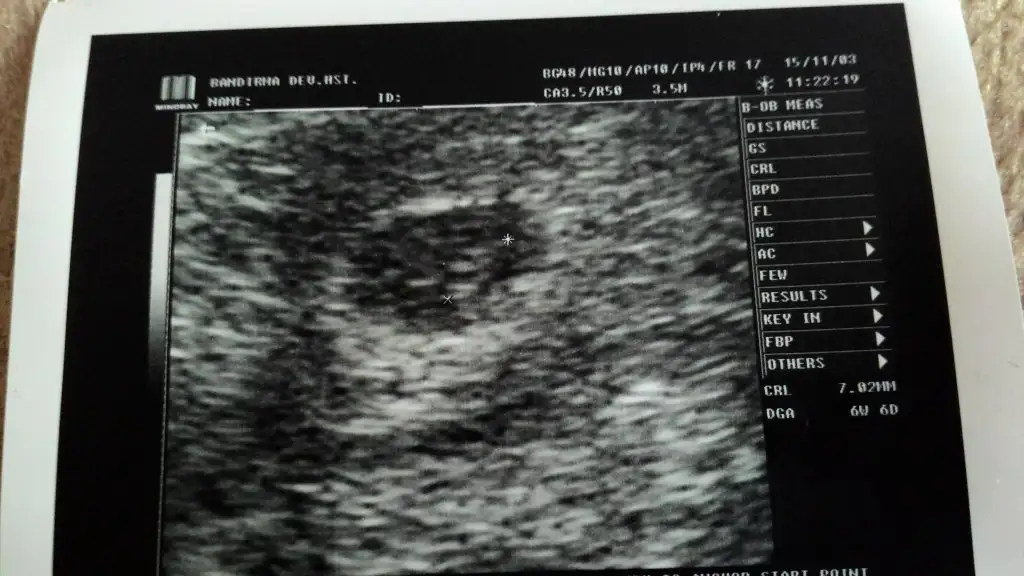

Gunaydin, evet bi suredir giremiyorum. Rapor aldim 3 hafta evdeyim 1 haftam kaldi bulantilrim cok. Medipole oznur hanima basladim. Esim degistirme dedi. Memnun kaldik. Hastanede cok yakin. Ama ben zpr geciriyrm bu bulanti donemini. Sen nasilsin canim. Hftaya c.tesi sabah tekrar randevum var.günaydın, görüşemedik canım ne yaptın tülay hanıma gidebildin mi hiç, yada medipole?